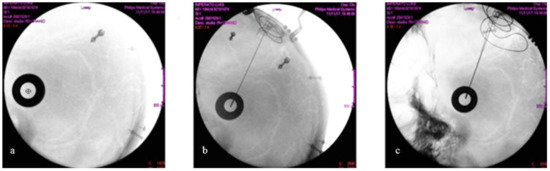

No asymmetry concerning the position of the distal tip of the two electrodes was detected intraoperatively (Figure 7) in the group of patients implanted under X-ray control, thus the electrodes were correctly positioned and symmetric when compared to each other. Their correct placement in the STN was further supported by the fact that the typical SEP waves that may be recorded in the STN through the electrode contacts (Figure 8) were found in each patient.

Figure 7.

(a) The latero-lateral X-ray image shows the alignment of the radiopaque fiducials. The screws applied to the skull for navigation are also visible. The centre of the circle (black cross) represents the target (i.e. the horizontal entry point). (b) The right electrode hits the target. (c) The final intraoperative control with the two electrodes (latero-lateral X-ray image), after their fixation to the skull with titanium microplates.

No significant difference was found in the Z coordinate in our patients when comparing the intraoperative X-rays controls to postoperative CT scans. Most likely, this was also due to our electrode fixation method, which uses titanium microplates (see the picture in Figure 8c, which was taken soon after the final electrode was fixed to the skull). The differences concerning the X and Y coordinates may have been caused by differences in the Z coordinate (depth) and might have been enhanced given the trajectory inclination along the anteroposterior and lateral directions. We have not considered anteroposterior X-ray controls for two reasons: firstly, because the X and Y coordinates are strictly dependent on the predetermined choice of the entry point and the trajectory inclination, and secondly because the presence of the Mayfield apparatus and the Nexframe tower do not allow for the alignment of the anteroposterior plane to take X-ray slides.